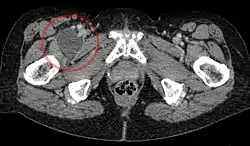

Iliopectineal bursa

The iliopectineal bursa or the iliopsoas bursa is a large synovial bursa that separates the external surface of the hip joint capsule from the normally just the tendon of the iliopsoas muscle.[1]

The most proximal of part the iliopectineal bursa lies on the iliopubic eminence of the superior pubic ramus. The iliopectineal bursa passes across the front of the capsule of the hip joint and extends distally downwards almost as far as to the lesser trochanter.[2]

The iliopectineal bursa frequently communicates by a circular aperture with the cavity of the hip joint.[1]

In 13% of all cases the iliopectineal bursa is partly separated by a septum into two cavities. Here the tendon of the psoas major muscle passes over the medial chamber and the tendon of the iliacus muscle runs over the lateral chamber.[2]

Inflammation of the iliopectineal bursa is called iliopectineal bursitis or iliopsoas bursitis.